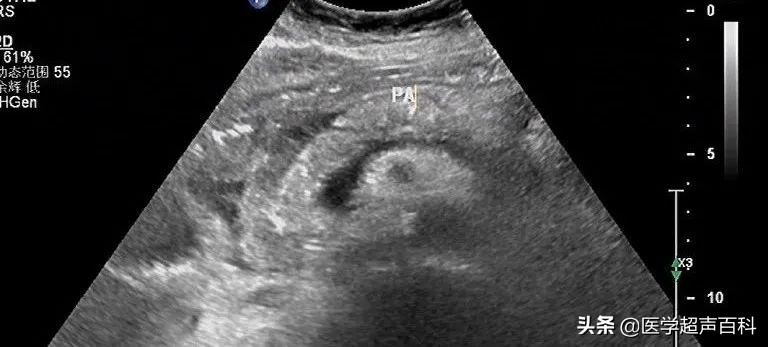

水肿型胰腺炎:胰腺稍大, 边缘规整,胰头、体部回声减低,分布前均质

急性胰腺炎声像图表现

(1)胰腺弥漫性或局限性增大,可失去正常形态,轮廓不清。

(2)内回声减低,呈弥漫分布的弱点状,中间有强弱不均、形态不整、边界不清的片状回声。严重水肿时呈透声暗区,似囊肿声像图。